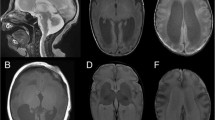

Clinical reports of 3 novel cases

For the purpose of this study the clinical course of three individuals, who presented between 1999 and 2016 at our Center of Developmental Neurology and Social Pediatrics for investigation of the etiology of developmental delay, was retrospectively summarized after pathogenic missense variants in TUBA1A had been identified. In summary, we present novel clinical data for two boys aged 13 years 7 months (individual i084n) and 11 years 6 months (individual i085n) and a 9 years 3 months old girl (individual i086n) with global developmental delay and neuroradiological abnormalities due to TUBA1A-associated tubulinopathy. The identification of the TUBA1A variant in the girl was part of a previous publication without detailed clinical description (reported as ID S_006) [16]. Narrative case reports with representative MRI planes for all three individuals and facial phenotype pictures for i086n (Additional file 1: Figure S1-S3) are provided in the Supplementary notes.

Additional file 1:

Figure S1. Cranial MRI planes of individual i084n. Figure S2. Cranial MRI planes of individual i085n. Figure S3. Cranial MRI planes and clinical pictures of individual i086n. Figure S4. Additional computational scores for TUBA1A variants. Figure S5. Analysis of the variant cluster around amino acid position 400. Figure S6. Comparison of computational scores for TUBA1A variants identified in fetuses and born individuals. Figure S7. Matrix plot of all HPO phenotype categories. Figure S8. Association plots for recurrently affected amino-acid positions and all neuroradiological features. Figure S9. Association plots publications describing ≥ 5 individuals and all neuroradiological features. Table S1. Barthel Index of Activities of Daily Living [3] of the 3 individuals with TUBA1A variants. (DOCX 2946 kb)